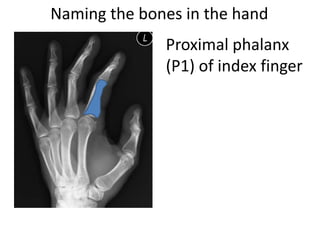

This document provides an overview of hand anatomy including:

- Naming the bones, joints, tendons, nerves and skin landmarks of the hand and wrist.